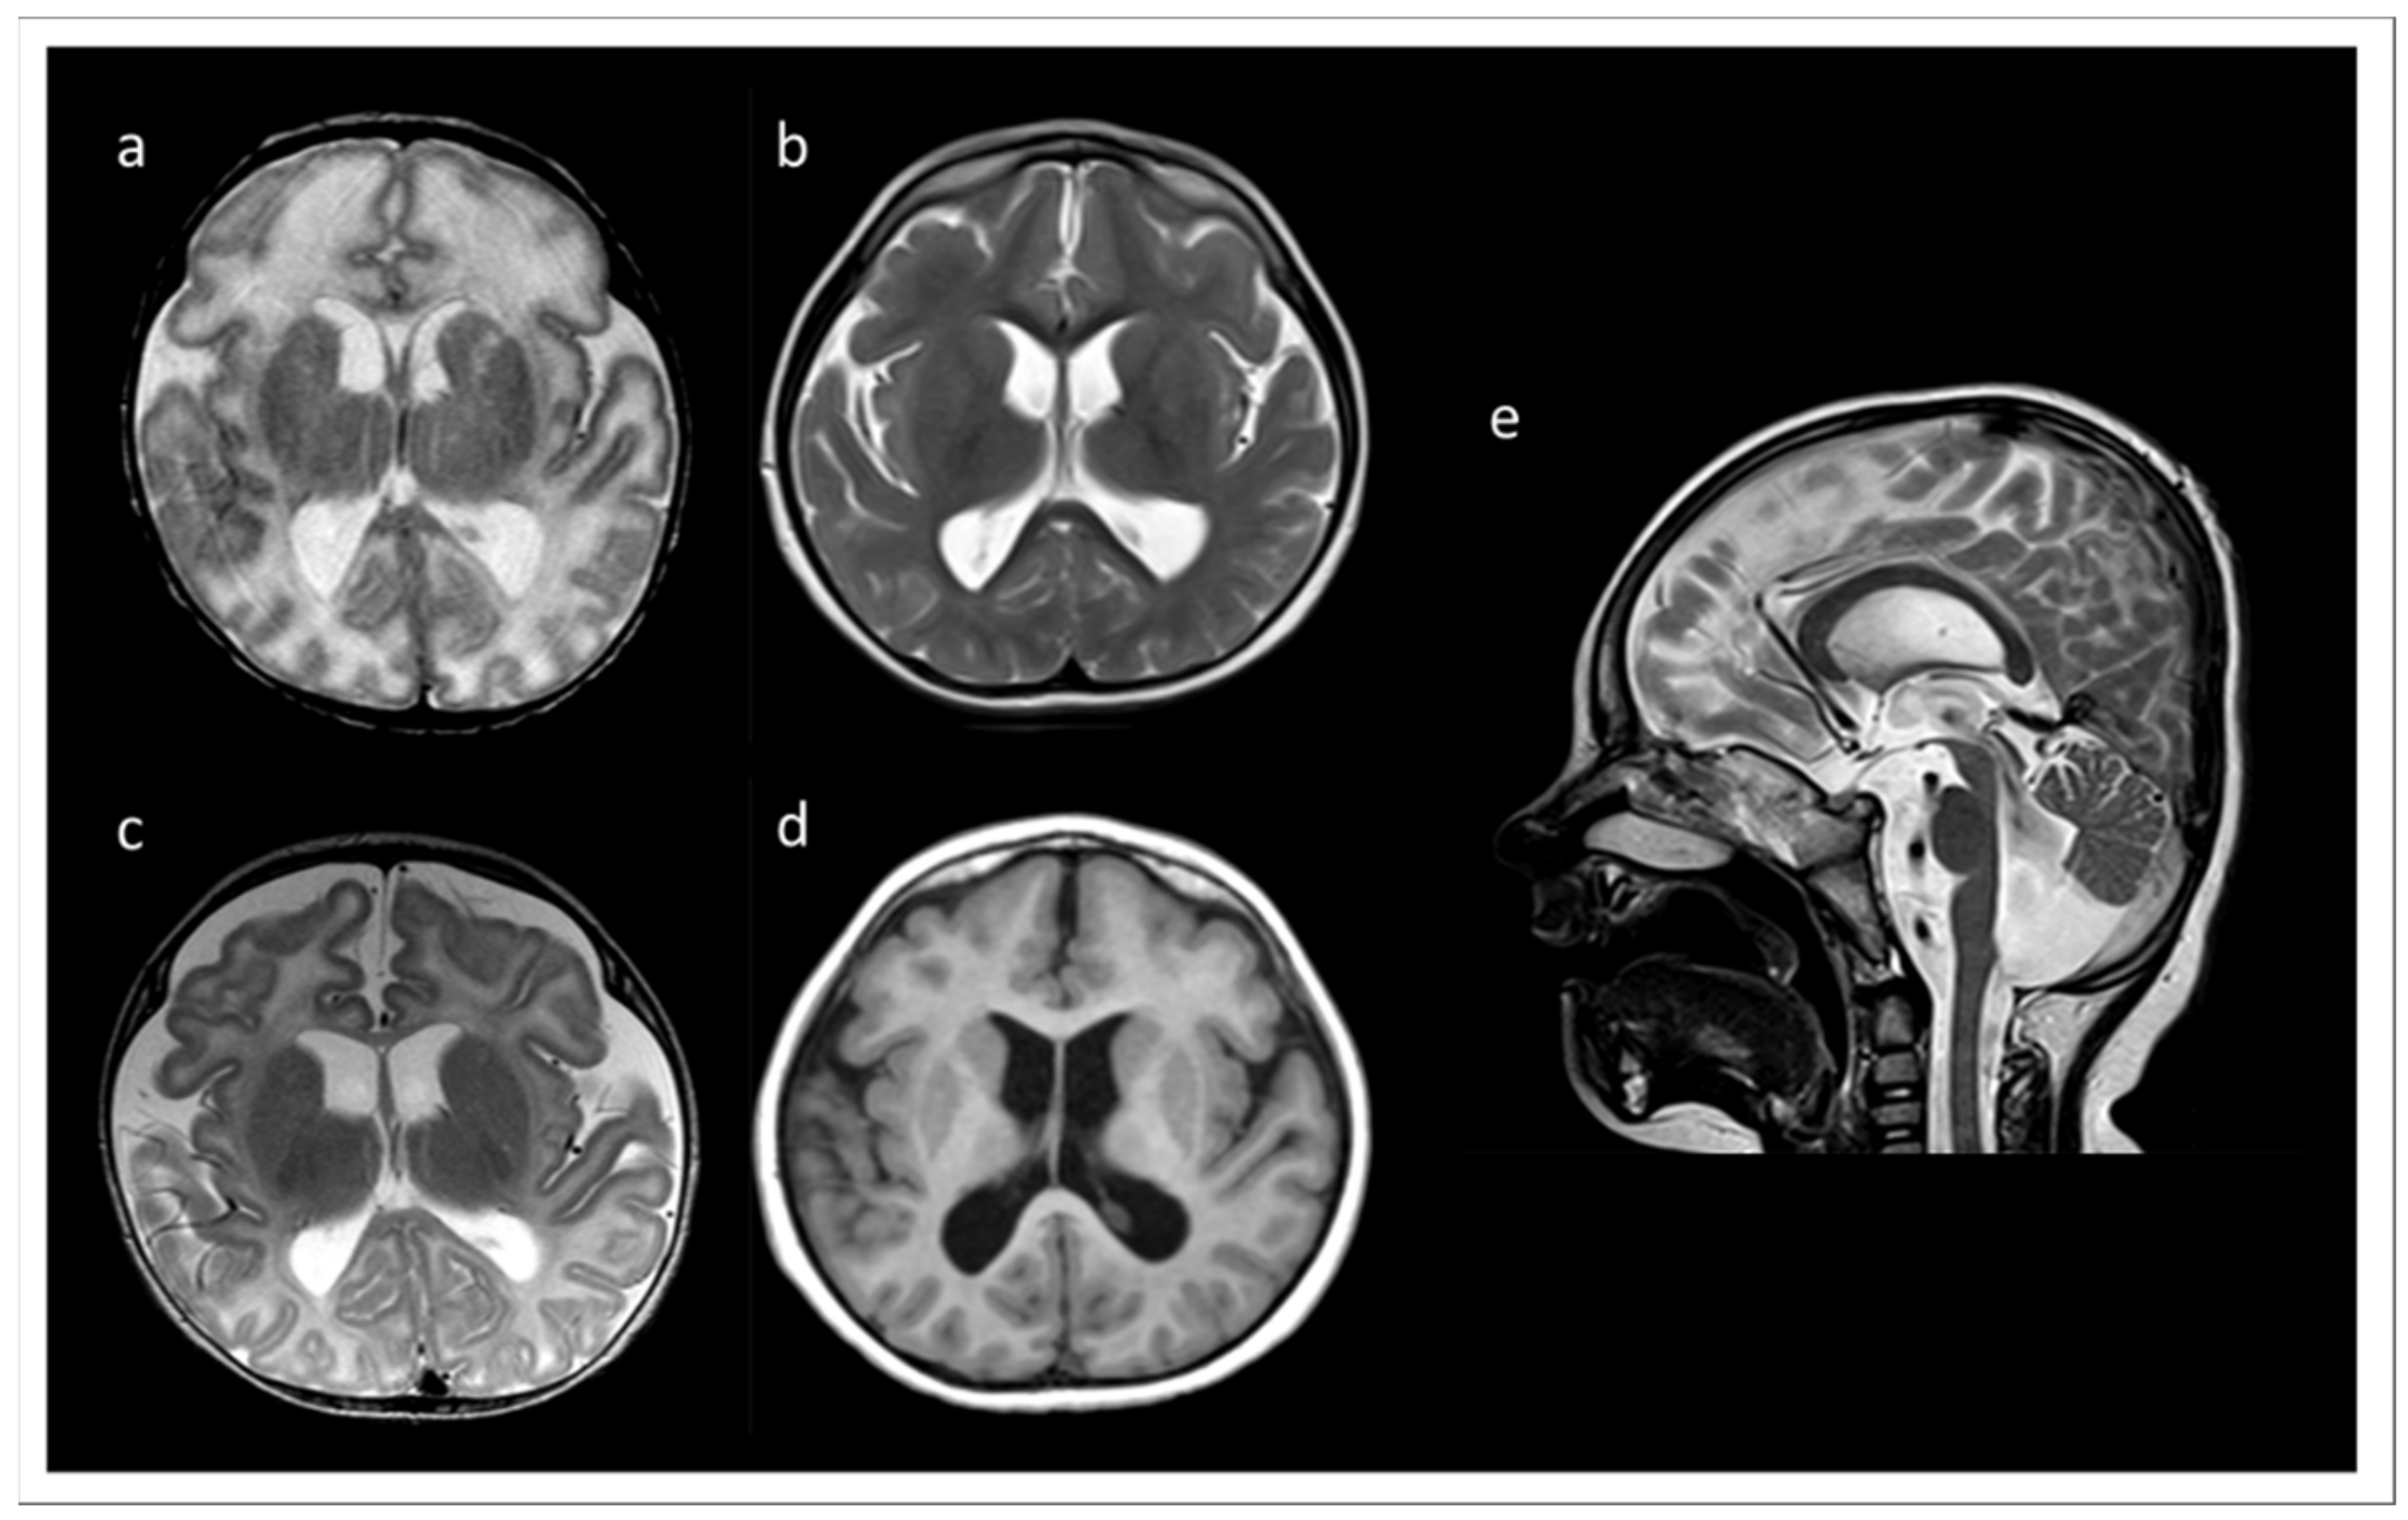

We report a six years old boy with a developmental disorder phenotype, born to non-consanguineous and healthy Lithuanian parents. No further family members were reported to be affected with similar symptoms. The IP was delivered by Caesarean section at 33 weeks and 2 days of gestation, because a pathological cardiotocographic (CTG) picture and dystrophy was detected. His birth weight was 1410 g (z-score −1.66), body length 42 cm (z-score −1.06), and head circumference 29 cm (z-score −1.45). The newborn patient was hospitalized over 9 weeks because of a profound drinking disorder with failure to thrive requiring tube feeding. In the first MRI at term equivalent age the cerebrum appeared swollen due to an immature sulcation with less numerous and broad gyri with shallow sulci, especially frontal. The T2 signal of the supratentorial white matter was significantly increased (Figure 1a). During follow up at the age of 3 months, the process of gyration and sulcation was completed. The brain was microcephalic with a simplified gyral pattern. Signs of myelination were slowly increasing, but still not age-appropriate (Figure 1b). At the age of 3.5 years, myelination was clearly advanced, but not yet complete (Figure 1c,d). There was concomitant ventriculomegaly, thickening of the corpus callosum, and pontine and vermis hypoplasia (Figure 1e).

Figure 1.

MRI records of the TARP-affected patient. (a) At term equivalent age the cerebrum was swollen with increased T2 signal of the supratentorial white matter and a simplified gyral pattern, especially frontal. In the further course, microcephaly with simplified gyral pattern and myelination delay were visible. (b) T2 at the age of 3 months. (c) T2 at the age of 3.5 years. (d) T1 at the age of 3.5 years. (e) T2 at 3.5 years of age showing concomitant ventriculomegaly, thickening of the corpus callosum, and pontine and vermis hypoplasia.